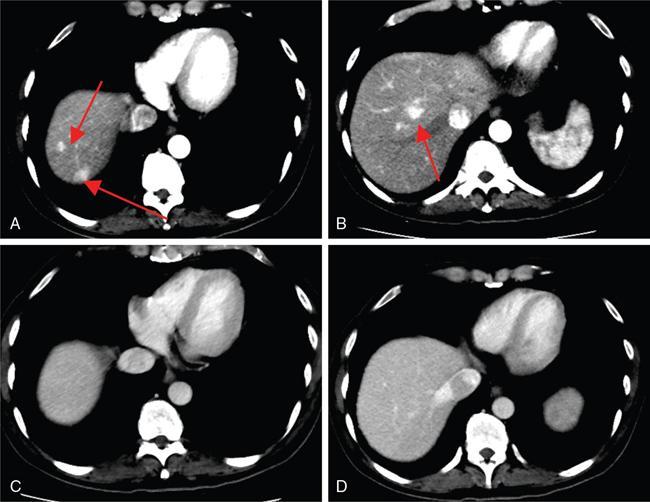

Ritu K. Kashikar, Shrinivas B. Desai, Pooja Punjani Vyas, Nilesh Doctor, Vivek Shetty Owing to advances in technology, focal liver lesions (FLLs) are increasingly encountered. Imaging particularly computed tomography (CT) and magnetic resonance imaging (MRI) play a vital role in diagnosis and characterization of FLL, thus avoiding unnecessary biopsies and interventions. Multiphase CT accurately diagnosis most liver lesions. Better soft tissue contrast and lack of ionizing radiation makes MRI a preferred modality in diagnosing FLLs. MRI with or without contrast for characterization of liver lesions regardless of preexisting liver disease has been assigned the highest rating as per American College of Radiology Appropriateness Criteria (Table 9.11.1). Solid lesions of epithelial origin Solid lesions of nonepithelial origin Pitfalls Cystic liver lesion Developmental cyst Infective cyst Miscellaneous Tmours of hepatocellular origin Tumours of nonepithelial origin Malignant cystic lesion Hepatic metastasis Ultrasound is often the initial modality for diagnosis and also the incidental detection of FLLs. Limitations to USG include the detection of small lesions less than 2 cm in size, particularly in patients who are cirrhotic or undergoing chemotherapy. Characterization of FLLs, involvement of crucial structures such as blood vessels, local staging and decisions such as operability are also not accurate with ultrasound alone and require confirmation with CT/MRI. The liver typically images in supine and left lateral positions. A curvilinear transducer with a frequency of 1.5 Hz is used. The subcostal diagonal, subcostal longitudinal or sagittal and transverse right intercostal lateral views are used. Right lobe of liver is imaged through an intercostal approach when the patient is taking deep inspiration. Subcostal view is used to image the three hepatic veins in one view. Transverse, longitudinal and oblique views of the liver are taken to image all the segments of liver. Colour and power Doppler have increased sensitivity for FLL detection, but sensitivity is still inferior to contrast-enhanced CT and MRI. The introduction of microbubble contrast agents (CAs) and the development of contrast-specific techniques have opened new perspectives in ultrasound of the liver. The technique is based on a new class of intravascular microbubble agents which contain perfluoro gases instead of air. This when combined with scanning modes sensitive to harmonic responses of microbubbles enable tissue signal suppression. The advent of the multislice technique and isotropic voxel have improved the spatial resolution of CT, allowing the recognition of small FLLs in difficult areas. Multislice CT has a sensitivity and specificity in the diagnosis of malignant FLLs of 63% and 64%, and 92 and 97%, respectively. Contrast media administration with dose based on the patient’s weight (approximately 600 mg iodine/kg of bodyweight), an iodine content of 350–400 mg/mL and a high injection rate of 4–5 mL/s are imperative to attain good contrast enhancement. Region of interest in the abdominal aorta and a threshold of 100 HU allows correct timing for threshold. A delay of approximately 18 s after the threshold provides the first arterial phase, allowing detection of hypervascular FLLs such as hepatocellular carcinoma (HCC). The late arterial phase is obtained approximately 10 s after the early arterial phase and shows progressive enhancement of hypervascular lesions, improving detection rate, while the optimal hepatic enhancement in the portal phase is reached approximately 50–60 s after the threshold. Portal venous thrombi are also best detected in this phase. The venous phase aids in the detection of washout, hepatic venous thrombosis. Delayed phase is often required in lesions such as cholangiocarcinoma and haemangioma, which show progressive enhancement (Table 9.11.2, Fig. 9.11.1). Delayed phase images are required for tumours such as cholangiocarcinoma and large haemangiomas, which reveal delayed enhancement. As mentioned previously, MRI is the modality of choice in diagnosis of FLLs. Most FLLs appear hyperintense on T2W1 images with varying intensity depending upon the water content and flow dynamics. FLLs are typically hypointense on T1W1 images with the exception of fat containing, haemorrhagic lesions and those containing chelates of metals like regenerating/dysplastic nodules. In- and opposed-phase images help in detection of intralesional fat. Diffusion-weighted images are beneficial particularly in noncirrhotic population and best suited in detection of metastasis. Postcontrast images obtained with extracellular agents are parallel to those obtained with CT (Fig. 9.11.2). The pre- and postcontrast MRI protocol is mentioned in Table 9.11.3. T2-weighted single-shot fast spin-echo (SE) T1-weighted in- and opposed-phase GRE Dynamic 3D T1-weighted FS spoiled GRE (in hepatic arterial, portal venous and equilibrium phases) There are two main categories of CAs used in liver imaging – the extracellular and the hepatocyte-specific (Fig. 9.11.3). Extracellular agents are more widely used and provide information similar to contrast-enhanced CT study. The advantage of the other category of CAs, that is, hepatocyte-specific agents, is the ability to provide this extracellular information with added benefit of delayed phase information. Tumours of hepatocellular origin with functioning hepatocytes take up and biliary excretion with take up and retain these agents appearing isointense to background liver. Lesions without functioning hepatocytes fail to retain contrast and hence appear hypointense to background liver on delayed phase. This allows better detection and characterization of focal liver lesion particularly those lesser than 2 cm (Table 9.11.4). Haemangioma is the most common benign hepatic tumour. The incidence in general population varies from 1% to 20%. Females have a higher preponderance with variable female to male ratios of 2:1 to 5:1. Imaging in particular MRI has high reliability in diagnosing classic haemangioma. The sensitivity and specificity of MRI is greater than 90% in diagnosis. The aetiology of haemangioma is unknown. Since haemangiomas are known to run in families, a genetic origin has been implicated, while other mesenchymal tumours are thought to be congenital. Most patients are asymptomatic and often the lesion is discovered as an incidental finding. Pain in the right upper abdomen is the most common complaint; others include loss of appetite, nausea, vomiting and abdominal discomfort. Symptoms are usually seen in large haemangiomas or those with complications. Liver function tests and tumour markers like AFP and CA19.9 are within normal limits. Blood-filled cavities of varying sizes lined by flat endothelial cells and supported by fibrous connective tissue are seen on histology. Three histological subtypes have been described: the capillary haemangioma, the cavernous haemangioma and the sclerosing haemangioma. The imaging features of a haemangioma depend on its size; typical haemangiomas are mostly less than 3 cm in diameter. Haemangiomas are hyperechogenic, homogeneous lesion presenting a posterior acoustic enhancement (Fig. 9.11.3). The hyperechogenicity of haemangiomas is related to the interfaces between vascular spaces, fibrous stroma and the slow blood flow. Typically, haemangiomas have slow flow and hence do not show vascularity on colour or power Doppler. The sensitivity and specificity of ultrasound in differentiating haemangioma from other malignant lesions are high, with values of approximately 94.1% and 80%, respectively, for lesions less than 3 cm in diameter. Unlike HCC, no flow is seen on colour Doppler. A peripheral echogenic rim around hypoechoic lesions can suggest haemangioma. On the contrary, perilesional hypoechoic rim called the target sign is seen in lesions such as metastasis (Table 9.11.5). Adenomas can be distinguished on the basis of the absence of posterior acoustic enhancement and characteristic pattern of peripheral vascularity seen in adenoma. Another differential diagnosis to be considered is focal nodular hyperplasia (FNH), which has the characteristic ‘spoke-wheel sign’. Contrast-enhanced ultrasound (CEUS) improves specificity for the diagnosis of haemangioma. The vascularity pattern with contrast-enhanced USG is similar to that seen with CT. The typical hemangioma (HH) shows peripheral nodular enhancement in the arterial phase with complete (but sometimes incomplete) centripetal filling in the portal venous and late phases. This particular pattern of enhancement helps in differentiating haemangiomas from other lesions like adenomas, FNH, HCC or metastasis. This characteristic enhancement pattern has a sensitivity of 98% for histologically proven HH. One should be aware that an HH can rarely have a centrifugal enhancement. Computed tomographic (CT) findings consist of a hypoattenuating lesion on nonenhanced images. Haemangiomas show peripheral discontinuous nodular enhancement on arterial phase of dynamic contrast-enhanced CT. The density of the nodules is equivalent to that of the aorta. Centripetal filling with is seen on venous phase, which progresses to uniform enhancement. The enhancement persists on delayed phase (Fig. 9.11.4). Washout of contrast on delayed phase is not seen in haemangioma and if seen, alternate diagnosis must be considered. This classical pattern of enhancement cannot be highlighted in very small lesions of less than 5 mm, which can be difficult to characterize. In patients with severe fatty infiltration of the liver, HH can appear hyperdense relative to the adjacent liver parenchyma on nonenhanced scan. Haemangiomas are hyperintense on T2-weighted images, which is identical to that of cerebrospinal fluid. T2 hyperintense signal is classically described as ‘light bulb bright’. Malignant lesions of the liver do not appear as bright on T2W1 images. They appear hypointense to adjacent liver on T1-weighted images. Long relaxation T2W1 images further improve accuracy in diagnosis of haemangiomas and help in differentiation from metastasis. Haemangiomas, unlike other liver lesions retain hyperintense signal on long relaxation T2W1 images. A threshold of 112 ms has 92% accuracy, 96% sensitivity and 87% specificity for differentiating haemangiomas from metastasis. On gadolinium administration, the enhancement pattern is similar to that seen with iodinated contrast on CT. Classic enhancement pattern in combination with characteristic T2 appearance are diagnostic for haemangioma (Fig. 9.11.5). Certain pitfalls exist in diagnosing haemangiomas using gadoxetate disodium. Due to the lack of hepatocytes, haemangiomas appear hypointense to the background liver on delayed hepatocyte phase and mimicking malignant process (Table 9.11.6). Lesions shown peripheral nodular arterial enhancement (Table 9.11.7): On fluorodeoxyglucose-positron emission tomography (FDG-PET)/CT, most hepatic haemangiomas appear low-attenuation lesions with FDG avidity equal to background liver parenchyma and are easily determined to be benign. However, a small percentage of haemangiomas may be FDG-avid. If an FDG-avid hepatic lesion demonstrates the characteristic enhancement pattern, this is consistent with an FDG-avid haemangioma. Technetium-99m pertechnetate-labelled red blood cell scintigraphy has high specificity in the diagnosis of haemangiomas. In this technique, there is decreased activity in haemangiomas on early images and increased activity on delayed blood pool images. Therefore, radionuclide scintigraphy has a sensitivity of 78% and an accuracy of 80% and may be a valuable tool when the diagnosis cannot be achieved with other imaging modalities. Large haemangiomas are often heterogeneous with internal clefts and septae. They are termed as giant haemangiomas when they exceed 4 cm in diameter. Discrepancies are there in definition with some authors defining giant haemangiomas as lesions greater than 6 cm or 12 cm in diameter. These may cause symptoms of abdominal pain and distension. These haemangiomas demonstrate changes such as haemorrhage, thrombosis, extensive hyalinization, liquefaction and fibrosis. The central cleft-like area may be due to cystic degeneration or liquefaction. On USG, they reveal heterogeneous echotexture. They are hypoattenuating and heterogeneous on nonenhanced CT with central areas of low attenuation. After intravenous administration of contrast material, the typical early, peripheral and globular enhancement is observed. These may show irregular or ‘flame-shaped’ discontinuous peripheral enhancement as opposed to typical nodular enhancement pattern seen in smaller haemangiomas. Although centripetal pattern of enhancement is seen during the venous and delayed phases, the filling-in incomplete. Central scars are defined in this subset of haemangiomas (Fig. 9.11.6). At MRI, T2-weighted images show a markedly hyperintense cleft-like area and some hypointense internal septa within a hyperintense mass. On delayed phase, incomplete filling and central scar are seen similar to CT (Fig. 9.11.7). Complications include intratumoural haemorrhage, inflammatory changes or consumptive coagulopathy (Kasabach–Merritt syndrome). These may warrant management such as arterial embolization or resection. This pattern is seen 16% of all haemangiomas, and is seen more often in small haemangiomas (42% of haemangiomas) <1 cm in diameter. CT and MRI show immediate homogeneous enhancement at arterial phase CT or contrast-enhanced MRI. The size of the blood spaces is the reason for difference in enhancement pattern. Smaller the lesion, smaller the size of blood spaces and faster the rate of spread of contrast material. These lesions usually show perilesional halo of hyperenhancement on the late arterial phase, which is believed to be due to arteriovenous shunting. Rapid arterial enhancement makes these haemangiomas difficult to distinguish from hypervascular metastasis (Table 9.11.8). However, washout of contrast is seen from haemangiomas on delayed phase (Fig. 9.11.8). Hepatic haemangiomas rarely demonstrate calcifications, while haemangiomas in other locations frequently demonstrate phleboliths. Calcified haemangiomas are mostly found incidentally. Calcifications may occur in the marginal or central portion of the lesion and consists of multiple spotty calcifications, which correspond to phleboliths. However, large, organized calcifications are also possible. Some calcified haemangiomas may demonstrate poor enhancement. Hyalinized hepatic haemangiomas are rare. It has been suggested that hyalinization represents an end stage of haemangioma evolution. These haemangiomas are usually asymptomatic. The radiological features of a haemangioma are completely altered ones hyalinization occurs; hence biopsy is often mandatory for diagnosis. Hyalinized haemangiomas show only slight high signal intensity on T2W1 images. There is lack of early enhancement on dynamic contrast-enhanced images (Fig. 9.11.9). Fluid–fluid levels within haemangiomas are very rare. Fluid–fluid levels are seen both with CT and MRI with inferior layer representing the red blood cells and superior layer unclotted serous blood. Dependent hyperdensity/T1 hyperintensities can be seen corresponding with dependent haemorrhage. Pedunculated haemangiomas are very rare. They can be asymptomatic or complicated by subacute torsion and infarction. Typical enhancement pattern and signal on T1 and T2W1 images are clues to the diagnosis. Capsular retraction is usually associated with malignant tumours such as cholangiocarcinoma, epithelioid haemangioendothelioma or metastases. Rarely, it has been seen in haemangiomas. A possible mechanism could be fibrous degeneration. Multiple haemangiomas are seen in 10% of cases and usually show classical imaging features. Fatty infiltration of liver may alter the imaging appearances of lesions. Haemangiomas appear slightly hyperechoic, isoechoic or hypoechoic relative to the fatty liver. At nonenhanced CT, the lesion may be hyperattenuating relative to the liver. Contrast-enhanced CT shows peripheral enhancement and delayed filling, an appearance similar to that of a haemangioma in a normal liver. Haemangiomas are less common in setting of cirrhosis and may be difficult to diagnose due to sclerosis. Complications are seen in 4.5%–19.7% and often seen in large lesions such as inflammation, coagulation within can lead to systemic disorders, haemorrhage would lead to haemoperitoneum, volvulus and adjacent organ compression. Irrespective of the size, treatment is indicated only for haemangiomas with significant symptoms, those developing complications, or when there is an inability to exclude malignancy. Attempt should be made to exclude other causes of the patient’s symptoms. The term focal nodular hyperplasia (FNH) was introduced in 1958 by Edmondson. In 1995, the International Working Party classified FNH with other regenerative lesions, and not a neoplastic lesion. It is defined as a nodule consisting of normal appearing hepatocytes occurring in a histologically normal liver. It is the second most common tumour of the liver after haemangioma with a reported prevalence of 0.9%. The lesion is more commonly seen in females with female to male ratio of 8:1. Multiplicity is seen in 20% of patients. The combination of multiple FNH lesions and haemangiomas is considered to be multiple FNH syndrome. Vascular malformation and vascular injury have been suggested as the underlying mechanism. An association with steroids has been denied more recently. FNH has been classified as classic and nonclassic varieties. These have been discussed in Table 9.11.9. Classic FNH is characterized by abnormal nodular architecture, malformed vessels and cholangiolar proliferation. Nonclassic FNH lesions lack one of the following classic features – nodular abnormal architecture or malformed vessels – but always show bile ductular proliferation. Classic FNH on gross appearance shows lobulated contours with multiple nodules surrounded by fibrous septae originating from a central scar, which contains a vascular malformation. On histopathology, nodular hyperplastic parenchyma is seen in classic FNH. Circular or short fibrous septae surround these nodules completely or incompletely. Thickening of the hepatic plates is seen. Fibrous connective tissue, cholangiolar proliferation with surrounding inflammatory infiltrates and malformed arteries, capillaries, vascular channels of undetermined type and veins are seen in the central scar. The arterial blood in FNH shows centrifugal distribution from anomalous central arteries. Fatty infiltration is seen in approximately 50% of lesions, while signs of hepatic steatosis are seen in approximately 20% of cases with classic FNH. Variable amounts of Kupffer cells are seen in both classic and nonclassic variants. Nonclassic FNH is heterogeneous and on gross appearance resembles adenomas in most cases, with vaguely lobulated contours and lack of a macroscopic central scar. The histology varies with subtypes. Subtypes of nonclassic FNH include telangiectatic type, mixed hyperplastic and adenomatous forms and FNH with cytologic atypia. The histological features of these are described in Table 9.11.10. At US, typical FNH is often not well visualized. The lesions may be slightly hypoechoic, isoechoic or slightly hyperechoic. The compressed liver tissue form a hypoechoic halo around the lesion, which appears more prominent in patients with fatty infiltration. A prominent central scar may improve the conspicuity of the lesions. Use of colour and power Doppler US shows vascularity in suspected FNH. On contrast-enhanced USG, FNH is hyperenhancing in the arterial and portal venous phases in more than 90% of cases. The arterial enhancement patterns include central (60%–70% of cases) or eccentric (<20% of cases) with centrifugal filling, but sometimes are homogeneous. Multiphase CT is an excellent modality for detection and characterization of FNH. These lesions classically show a lobulated contour. At unenhanced CT, the lesions are either hypoattenuating or isoattenuating to the surrounding liver. In the arterial phase, the lesions show homogeneous intense enhancement except the central scar and fibrous septa. In the portal and later phases, the lesions become more isoattenuating with the surrounding liver. The central scar reveals enhancement on delayed phase (Fig. 9.11.10). This feature helps distinguish from other lesions with central scar-like fibrolamellar carcinoma. A vascular malformation can be seen in the central scar in some cases (Fig. 9.11.11). There may be enlarged hepatic veins in the vicinity of the mass. FNH do not have portal venous drainage. The drainage is essentially into hepatic venules, hence the enlarged adjacent veins. The central scar is often not identified in small FNH lesions. In a study, 80% of FNH lesions less than 3 cm lacked visible central scar. The sensitivity and specificity of MRI in diagnosis of FNH are 70% and 98%, respectively. The central scar is more often detected with MRI than with CT (78% and 60%, respectively). FNH is typically iso- or hypointense on T1-weighted images (94%–100%) and is slightly hyperintense or isointense on T2-weighted images (94%–100%). The lesions may not be very conspicuous on T2W1 images. The central scar is hyperintense on T2-weighted images in 84% of cases. FNH shows intense homogeneous enhancement in the arterial phase. The enhancement pattern in arterial phase may be nodular, resembling a popcorn, the result of intralesional fibrous septae. Mosaic pattern of heterogeneous enhancement seen in malignant lesions is not seen in FNH. Central vascular malformation may be seen in early phases. These lesions classically fade to isointensity on delayed phase with the exception of the central scar (Fig. 9.11.12). FNH may show a pseudocapsule, which results from compression of the surrounding liver parenchyma by the FNH, perilesional vessels and inflammatory reaction. The pseudocapsule may show enhancement on delayed contrast-enhanced images. A central scar is present at imaging in most patients with FNH. The central scar is hyperintense on T2W1 and hypointense on T1W1 images. The presence of inflammation and vessels within the scar are responsible for the hyperintense signal (Fig. 9.11.13). The scar does not enhance on early phases of contrast study and shows enhancement on delayed phases of dynamic study. The scar is absent in 30% of cases. The hepatocyte-specific CA gadoxetate disodium can be useful in distinguishing FNH from other lesions like adenomas. Densely packed functioning hepatocytes and abnormal blind-ending bile ductules in FNH result in contrast retention and delayed biliary excretion. FNH often shows enhancement on delayed images using gadoxetate disodium, and along with radiating fibrous septae, it may result in a characteristic spoke-wheel appearance. On the contrary, hepatocellular adenomas (HCAs) are usually hypointense to liver on hepatocyte phase images because they lack bile ductules. Superparamagnetic iron oxide (SPIO) is a negative reticuloendothelial-specific CA taken up primarily by the hepatosplenic Kupffer cells. This agent shortens T2 relaxation time predominantly, leading to a significant decrease of SI of normal hepatic. FNH contains Kupffer cells and hence shows significant signal drop after administering SPIO. This CA is, however, not commonly used particularly with advent and increased usage of hepatocyte-specific agents (Table 9.11.11). These lesions have high signal intensity on T2-weighted images, a central scar with low signal intensity on T2-weighted images, a prominent pseudocapsule and incomplete intense enhancement of the lesion. Extreme heterogeneity can be seen in these lesions leading to difficulty in distinguishing from malignant lesions such as HCC and cholangiocarcinoma. Biopsy and histopathology diagnosis are often needed in this subset. Telangiectatic FNH may show areas of haemorrhage. A French study has reported an association of 23% between FNH and haemangiomas. The incidence of coexistence of FNH and adenoma is lower (3.6%). There have also been reports of rare associations of FNH with other types of vascular anomalies like congenital absence of the portal vein, inflammatory pseudotumours of the liver, hepatic vein thrombosis and intrahepatic arteriovenous shunting. Imaging differentials include HCA and other lesions with central scar like fibrolamellar carcinoma, HCC and giant haemangiomas (Table 9.11.12). FNH shows intense arterial phase enhancement and isodensity/isointensity on delayed phase, this feature helps in distinguishing from adenoma, which usually are hypoattenuating on the delayed phase. T1 hyperintensity seen in adenomas is not seen on FNH. Biopsy is recommended in cases where radiological features are atypical and distinguishing from malignant lesions like HCC cannot be made on the basis of imaging findings alone. As there is no risk of malignant transformation and complications are rare, FNH does not need treatment. Patients with large FNH causing compression of adjacent organs or occurrence of torsion in a pedunculated FNH may need surgical resection. Also, patients with diagnostic dilemma may be considered as surgical candidates. Adenoma is a less common benign primary neoplasm of the liver. Women of childbearing age taking oral contraceptives are considered at highest risk; however, it can occur in other women as well as men. Hepatic adenomas (HAs) were particularly associated with the use of older generation of OC pills with high-oestrogen content. Adenomas have also been reported to occur in men secondary to anabolic steroid/androgen use. Clomiphene, danazol and testosterone in patients with Fanconi anaemia (FA) and without FA, Klinefelter’s syndrome, glycogen storage disorders (GSDs) I, III and IV, alcohol and metabolic syndrome are other hormonal therapies and conditions associated with adenoma. Development of >10 adenomas in a patient is defined as hepatocellular adenomatosis (Fig. 9.11.14). Germline mutations of hepatocyte nuclear factor (HNF)-1 alpha and patients with type 3 maturity onset diabetes of young (MODY-3) may predispose. HCA has been categorized into three distinct subtypes based on genetic and pathologic features. These have been discussed in Table 9.11.13. Some exhibit both β-catenin activation and inflammatory features. Patients are usually asymptomatic at the time of diagnosis but some present with abdominal pain, haemorrhage, abnormal liver function tests or seldom with a palpable mass. HCA associated with haemorrhage may present with acute abdominal pain, elevated liver enzymes and hypovolemic shock. Signs of chronic anaemia and/or ‘systemic inflammatory syndrome’, characterized by fever, leukocytosis and elevated serum levels of C-reactive protein can be seen in patients with inflammatory HCA. Inflammatory HCAs are associated with a definitive increased risk of bleeding (>30%) and a risk of malignant transformation (5%–10%). The highest predilection for malignant transformation of all HCAs is seen in β-catenin activated subtype. On gross appearance, adenomas are well-circumscribed often encapsulated lesions with size varying between 1 and 30 cm. Lesions may be solitary or multifocal. They typically arise in nonfibrotic liver, however, the inflammatory subtype has been reported in the background of cirrhosis The cut surface of HA may be tan-yellow or red-brown depending upon the presence of steatosis or peliosis/haemorrhage/old haemorrhage, respectively. Sheets of benign-appearing hepatocytes with interspersed thin-walled, unpaired arteries are classically seen in HCA. Other variable features are steatosis, inflammatory cell infiltrate, sinusoidal dilatation, myxoid changes and presence of pigments such as bile pigment, lipofuscin or Dubin–Johnson-like pigment (Table 9.11.14). The typical small HCA is isoechoic in comparison to the surrounding liver parenchyma. Adenomas with high lipid content are hyperechoic on ultrasound. Intratumoural haemorrhage can also result in increased echogenicity and heterogeneity, or cystic areas. Calcifications are seen as hyperechoic foci with acoustic shadowing. Peripheral peritumoural vessels and intratumoural vessels with a flat continuous or triphasic form are seen on colour Doppler. FNH does not show this pattern of vascularity and hence this finding may be useful in distinguishing the two disease entities. On contrast-enhanced USG, arterial phase reveals centripetal or diffuse enhancement. Telangiectatic HCA with or without inflammation typically exhibit iso- or hyperenhancement in comparison to the surrounding liver parenchyma. Hypoenhancement is seen in portal venous phase with delayed washout in all subtypes. USG and contrast-enhanced USG features of histologic subtypes have been described. HNF-1α-inactivated HCAs are hyperechoic due to fat content and may be misdiagnosed as haemangiomas. The enhancement pattern is however that of arterial enhancement. With venous washout in contrast to haemangiomas which show portal venous hyperenhancement. On CEUS, telangiectatic HCA with or without inflammatory changes shows central multilocular vessel supply similar to FNH. These lesions might show centrifugal hyperenhancement during the early arterial phase which may persist on portal venous phase. Nevertheless, most adenomas are not specifically diagnosed at US and are usually further evaluated with CT or MRI. Multiphase CT is a good diagnostic modality in diagnosis of HCA. Fat or haemorrhage can easily be identified on unenhanced images. CT evidence of fat within the adenoma is seen in only about 10% of cases. Lesions show strong arterial enhancement and subcapsular feeding vessels. Enhancement is more heterogeneous in larger tumours and those with internal haemorrhage. The enhancement usually does not persist in adenomas because of arteriovenous shunting (Fig. 9.11.15). MRI is the modality of choice in diagnosis of adenomas and distinguishing various subtypes. Although the lesions can reveal varying signal on T1W1 images, recent reports have suggested that most adenomas are bright on T1-weighted images, 77% of cases in a study by Paulson et al. Other studies have, however, lesser incidence of T1 hyperintensity varying from 35% to 59%. Heterogeneous signal on TW1 images may be due to areas of increased signal intensity resulting from fat (36%–77% of cases in different series) and haemorrhage (52%–93%). Forty-seven to seventy-four per cent of HCAs are predominantly hyperintense relative to liver on T2-weighted images (Fig. 9.11.16). Majority of lesions are, however, heterogeneous owing to areas of haemorrhage and necrosis. Contrast-enhanced dynamic MR study shows early enhancement with peripheral subcapsular vessels. MR appearances can vary depending on the histological subtype (Table 9.11.15). On plain MRI, inflammatory HCA is often hyperintense on T2W images and hypointense on T1W sequence corresponding to areas of sinusoidal dilatation and inflammatory infiltrates. Foci of fat appear as areas of signal drop on opposed-phase images. They are hypervascular masses with persistent enhancement on dynamic study. Variable update of contrast especially at the periphery may be seen on hepatobiliary phase. Marked T2 hyperintense signal with persistent delayed enhancement has high sensitivity and specificity of 85% and 87%, respectively, for the diagnosis of inflammatory subtype. Peripheral hyperintensity on T2W1 images reflects the abnormal ductal reaction with altered biliary excretion and has been described as ‘atoll sign’ (Fig. 9.11.17).

CT

1. Giant haemangiomas

Imaging.